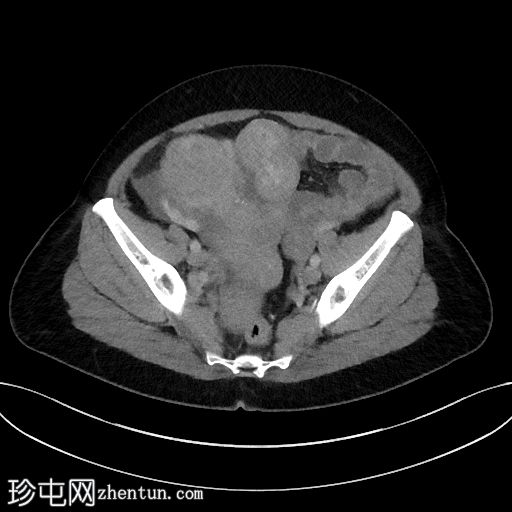

6个月前CT检查

CT

既往CT显示子宫内有多发性肌瘤,但在子宫右侧一个较大的肌瘤内可见一处不典型、中心低密度区。

无腹水。